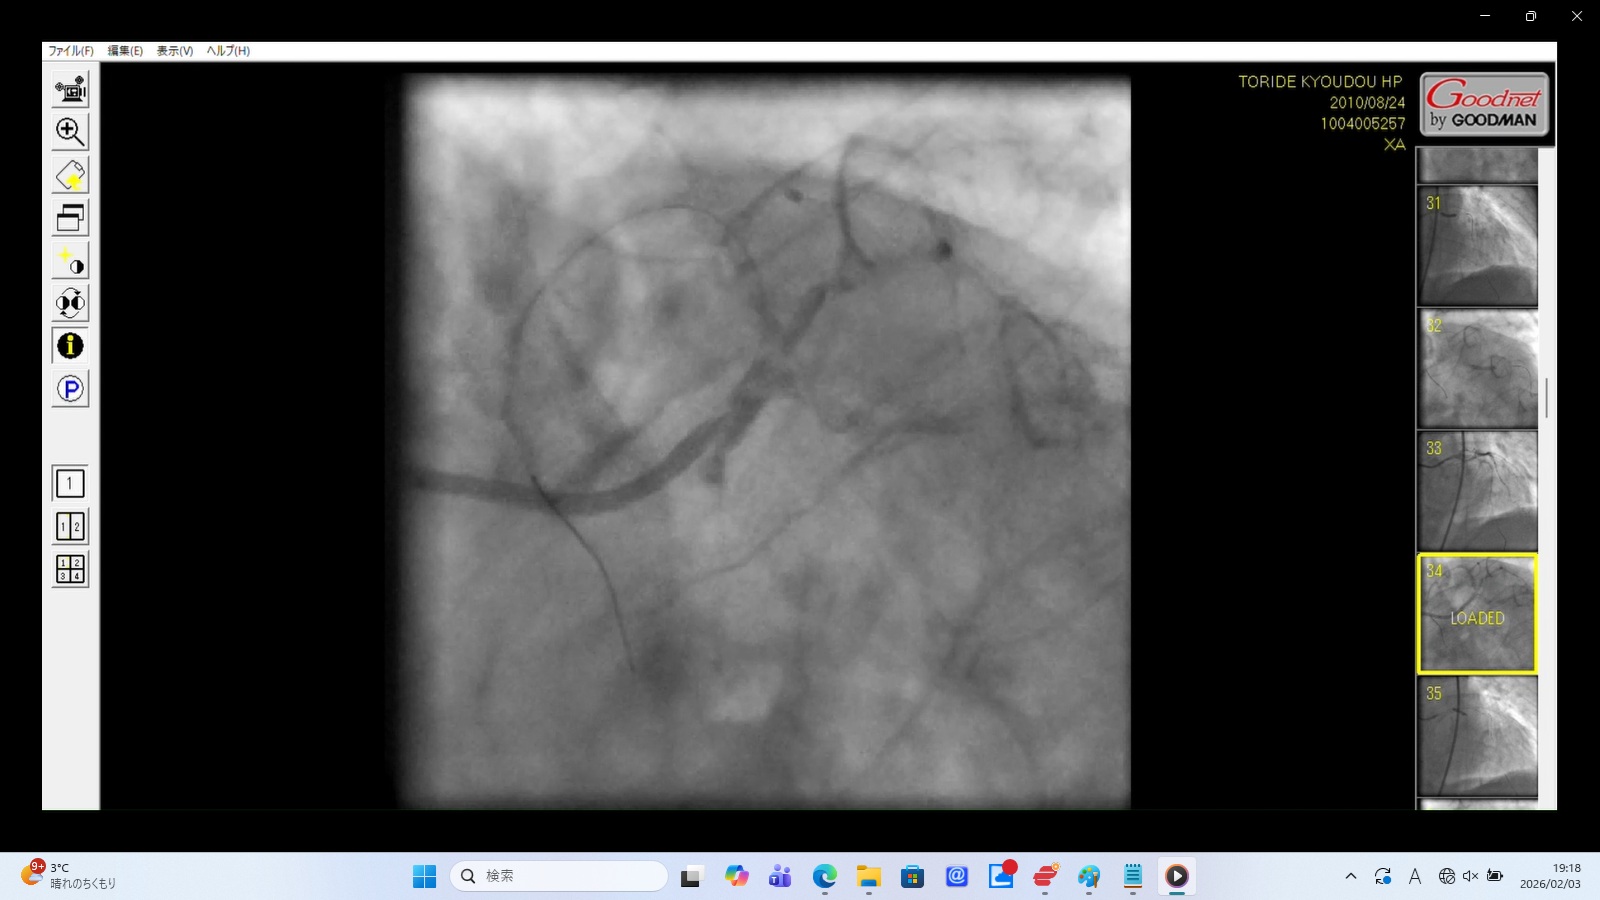

左前下行枝解離・穿孔、左冠動脈主幹部解離・損傷・完全閉塞、ステント様人工物の血管外脱落などの所見あり。 術者の岩井利之医師は「治療は成功した」と偽り、これらの大事故・大損傷を隠蔽した。救命のためには心臓血管外科での緊急手術が必要な状態であったはずだが、医師らはその手配をせず放置した。

血管外に脱落した浮遊する人工物

左冠動脈前下行枝(LAD)の穿孔

左冠動脈主幹部(LMT)の完全閉塞

22時35分に開始され、右橈骨動脈にガイドワイヤーを挿入して手技が開始されたが、 冠動脈にアプローチできず、右大腿動脈から挿入された。その間、アプローチが失敗した時間帯のPCI画像が 存在せず、ここで大事故を起こした証拠であるこの間の画像が抜き取られた可能性が疑われる。 PCIは3時間と長時間を要し、その間の放射線被曝量も人体に深刻な影響を与えるほど大量であった。 PCIの動画を確認すると左冠動脈主幹部解離・損傷・閉塞、左冠動脈前下行枝解離・穿孔、 左回旋枝への血栓閉塞、ステント様人工物の血管外落下など多数の致命的な大事故が認められた。 救命のためには心臓血管外科での開胸手術が必要のはずであったが、PCI終了後、医師は遺族に対して「治療は無事成功した」としてこの大事故を隠蔽し、心臓血管外科への手配をせずに放置し談笑していた。